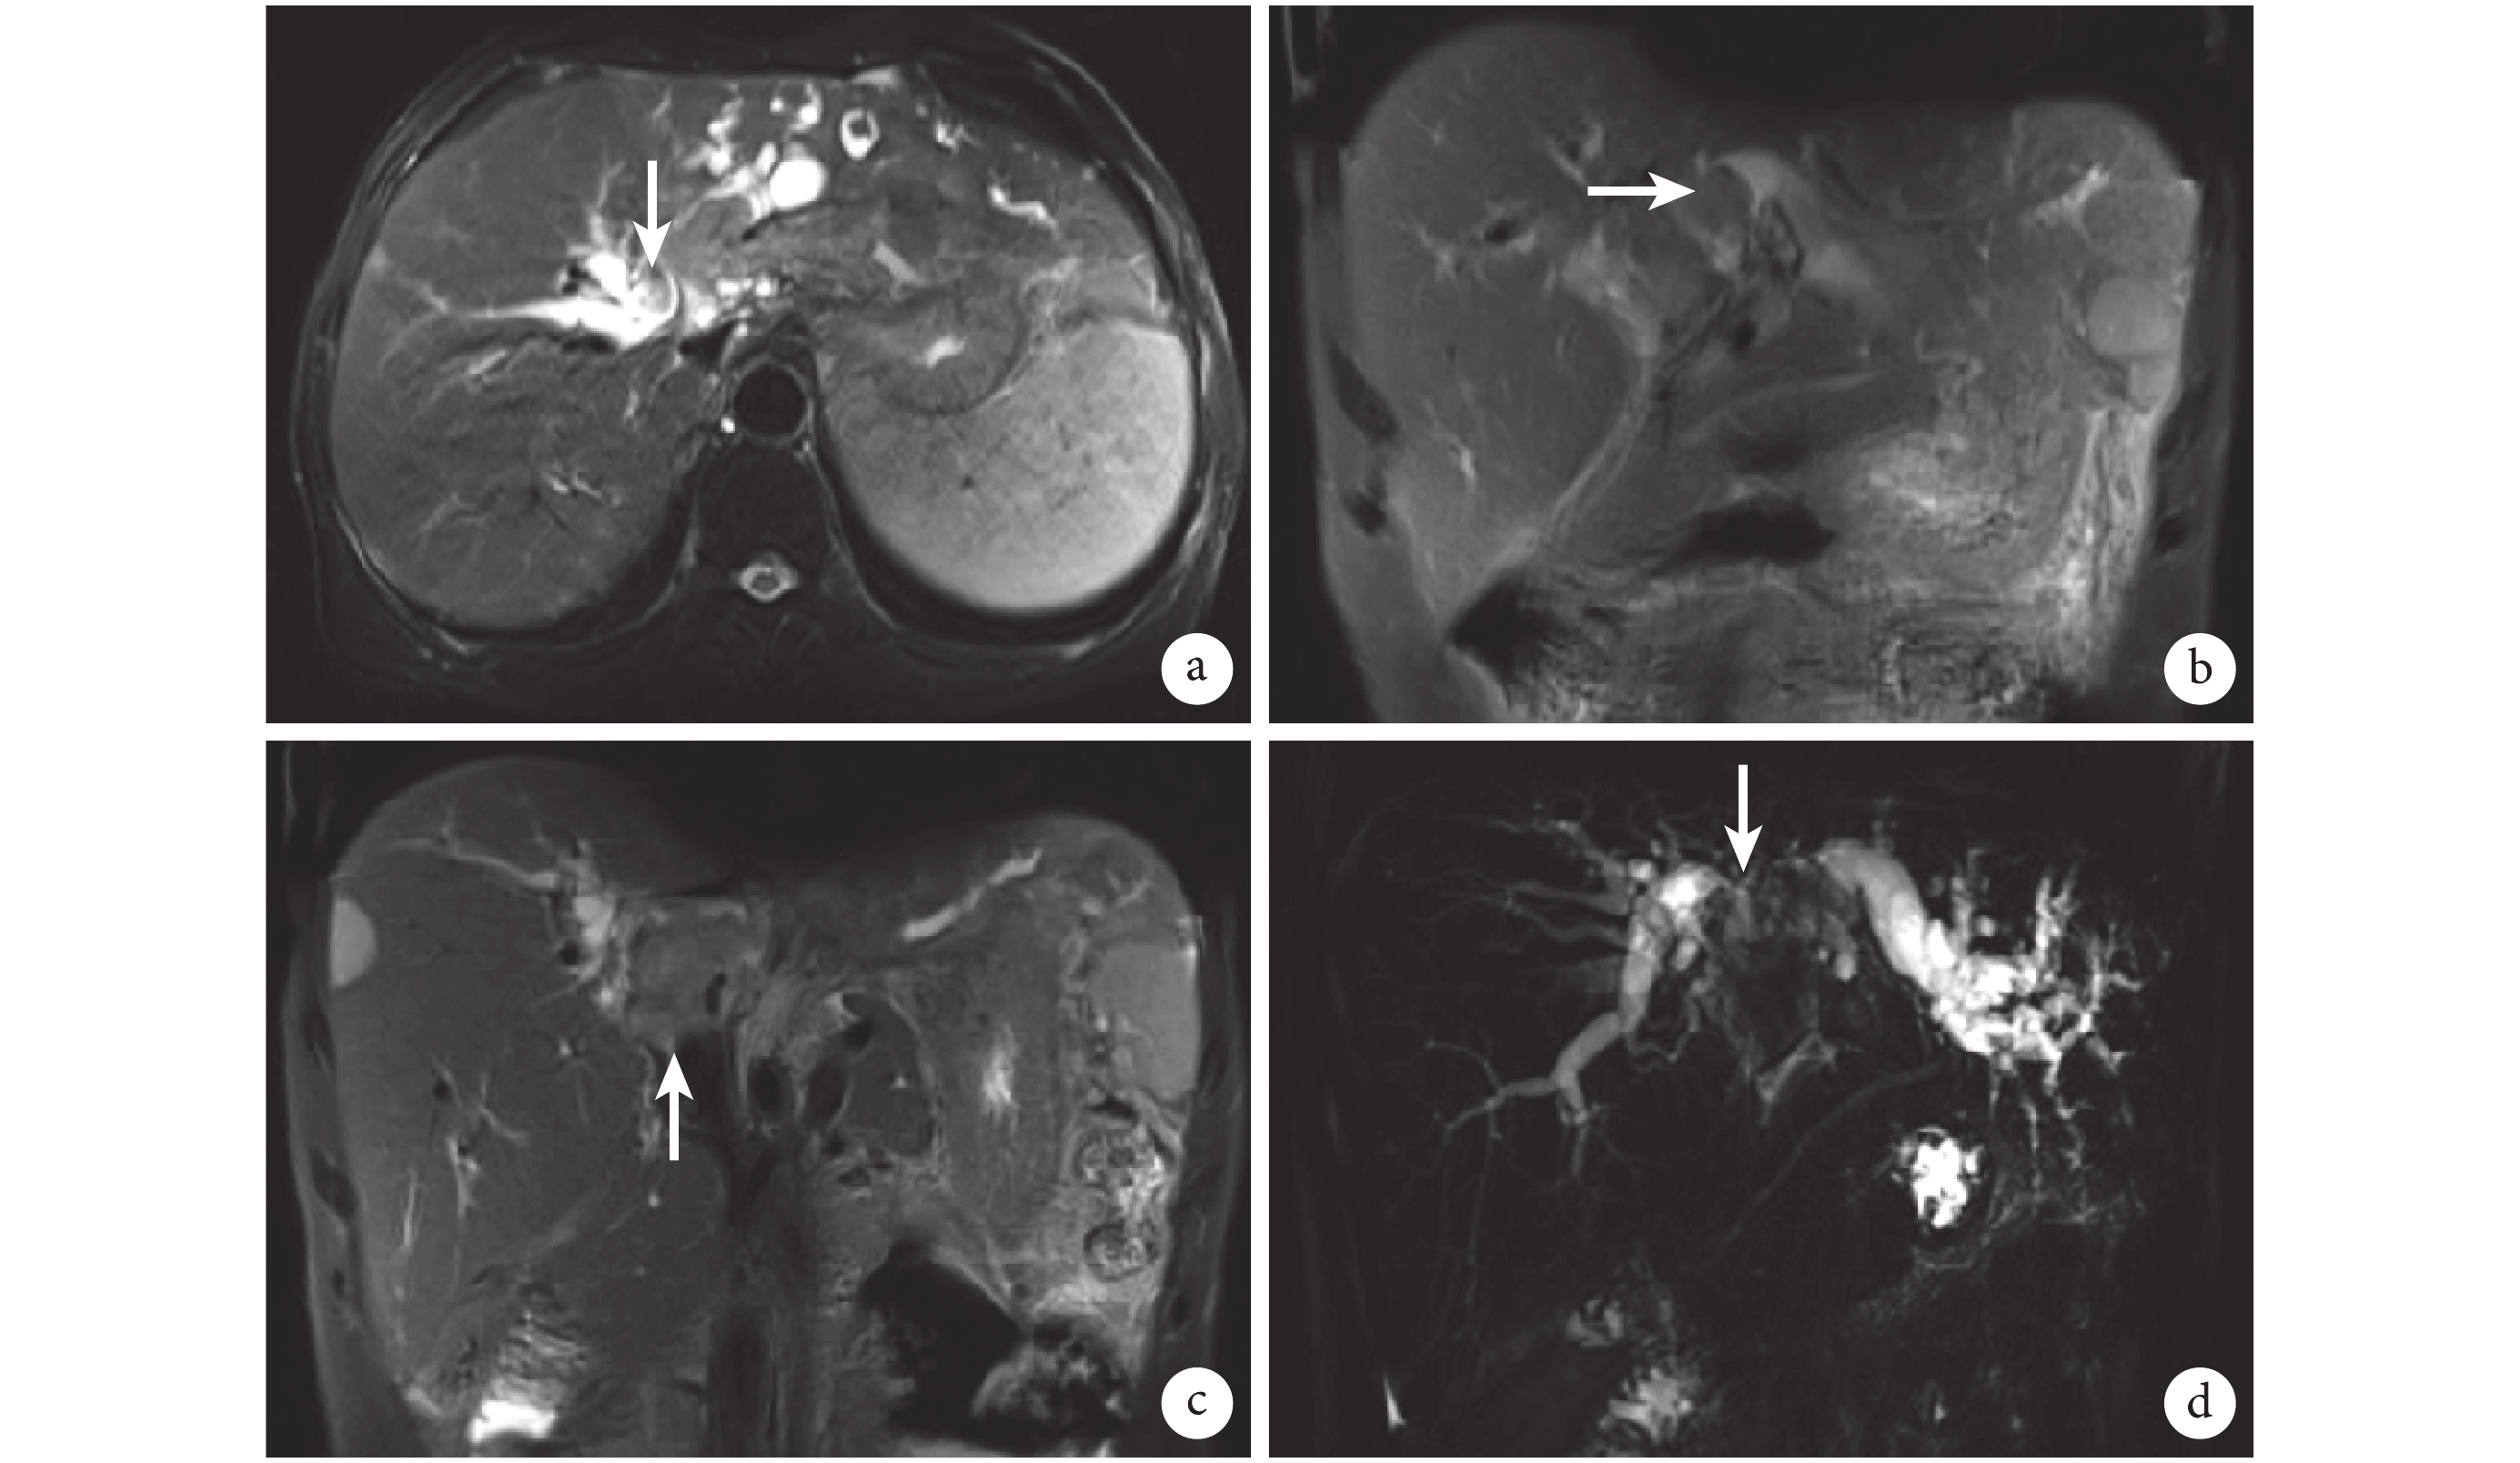

四川省腫瘤醫院影像科任靜主任醫師認為:患者的 MRI 圖像提示肝門區見一 3.7 cm×2.4 cm 大的實性占位,并向右肝管和左肝管內延伸;腫瘤向左肝管內延伸至左外葉膽管,向右延伸至膽管右前支和右后支匯合處,向下延伸至膽總管中段(圖 2);門靜脈左右支、肝動脈左右支及其主干均未見腫瘤侵犯(圖 3),肝門未見腫大淋巴結;脾臟明顯增大。MRI 掃描的 1~3 個層面中見左肝外葉有一 4.5 cm×4.5 cm 大的實性結節,動脈期明顯強化、門靜脈期強化減弱(圖 4),影像學考慮 HCC,因此之前的影像學閱片診斷錯誤。

a:BDTT 延伸至膽管右前、右后分叉處(白箭);b:BDTT 侵犯左肝外葉膽管(白箭);c:BDTT 延伸至膽總管內(白箭);d:BDTT 位于左右肝管及膽總管匯合處(白箭)